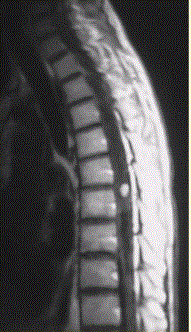

问题 患者女,45岁,胸部不适。影像学检查结果如下图所示。 对病变定位、定性诊断有价值的征象为

选项 A.脊椎增粗 B.邻近蛛网膜下腔变窄 C.病变边界清晰 D.病变特点为一个大囊,其内见一明显强化的结节影 E.病灶内有分隔 F.病灶内可见明显结节样强化

答案 ABCDF

解析 ABCDF